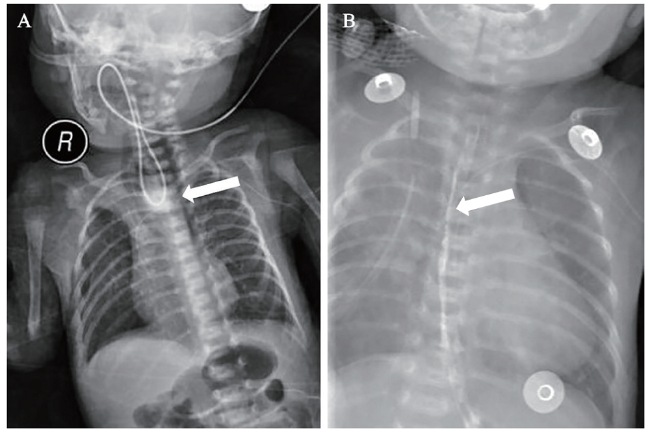

2019年11月27日患者行子宫下段剖宫产娩出一女婴,孕33+3周,羊水量约2500 mL,新生儿阿普加评分8 ~ 9分,出生体质量1990 g。婴儿因早产于出生后转入新生儿科。出生后2 d患儿出现奶汁反流现象,口腔中有大量透明黏性分泌物及白色泡沫状分泌物。X线胸片提示颈部及上纵隔投影区迂曲状管状投影。结合临床症状,高度怀疑患儿存在先天性食管闭锁,遂行上消化道碘水造影,结果提示造影剂聚集于食管中段,约第3 ~ 4胸椎水平,延时透视观察造影剂未见明显下行,考虑食管中段闭锁,见图1A。患儿遂转至小儿外科进一步治疗,于2019年12月9日全身麻醉下行食管-气管瘘修补术+食管端端吻合术。术后2周复查上消化道碘水造影,提示造影剂顺利通过食管,未见造影剂外漏,见图1B

图1 一例先天性食管闭锁新生儿的消化道造影结果

注:A为术前造影,经患儿胃管注入造影剂约2 ~ 3 mL,可见造影剂聚集于食管中段,约第3 ~ 4胸椎水平,延时透视观察造影剂未见明显下行,可见胃管返折,考虑食管中段闭锁(白色箭头所示);B为食管吻合术后造影,于患儿口腔内注入适量造影剂,患儿吞咽时造影剂可顺利通过食管进入胃内,未见造影剂明显外漏征象(白色箭头所示)。